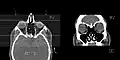

CT scan of the paranasal sinuses with coronal reconstruction (right) and axial planning data (left).